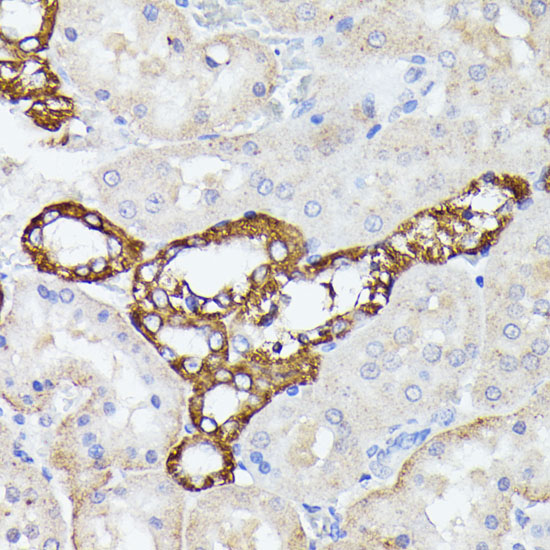

Immunohistochemistry of paraffin-embedded rat kidney using LTF at dilution of 1:100 (40x lens).